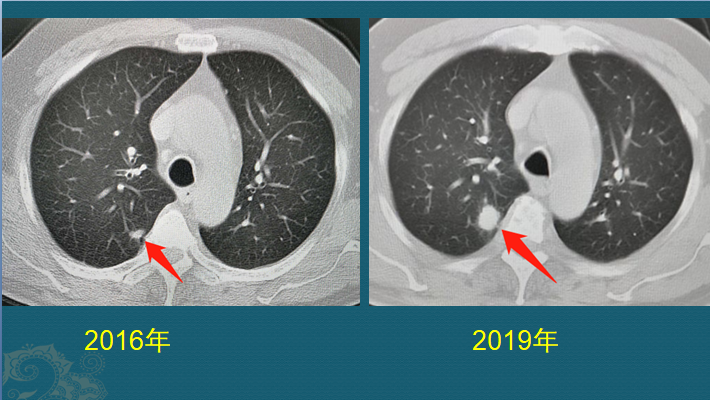

右肺结节术后证实为肺癌左肺还有病灶也会是癌吗